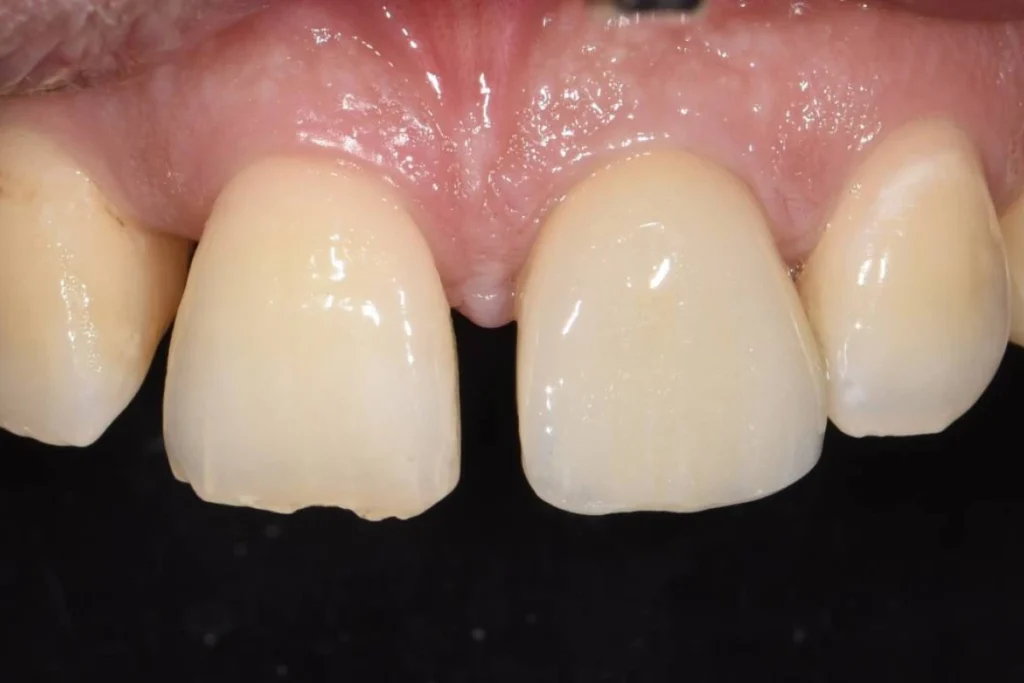

Cas clinique 3 – Mise en place d’un implant dentaire le jour de l’extraction

Nous vous présentons le cas de Mme B. 53 ans, qui consulte suite à des douleurs sur sa molaire supérieure gauche.

Après un examen clinique et radiographique, le verdict tombe… la dent n’est malheureusement plus conservable.

Après lui avoir exposé les différentes solutions, Madame B. souhaite remplacer sa dent par un implant. C’est la solution de choix pour retrouver une dent fixe sans avoir à abimer les dents de part et d’autre. L’analyse du scanner nous permet de proposer à Madame B. une extraction implantation immédiate. Il s’agit de réaliser en une seule et même séance l’extraction de la dent condamnée et la mise en place de l’implant dentaire.

Cela permet d’éviter une 2ème chirurgie à notre patiente et de raccourcir la durée du traitement de plusieurs mois. Un comblement osseux est réalisé le jour de l’intervention.

3 mois après la pose de l’implant, la patiente peut retrouver une dent fonctionnelle et esthétique.